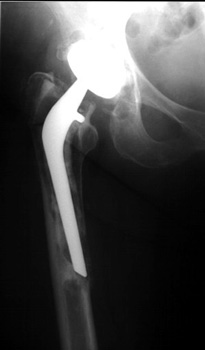

FEMORAL STEM POSITION

• Varus positioning

• Valgus positioning

Varus Normal Valgus

Varus

Valgus